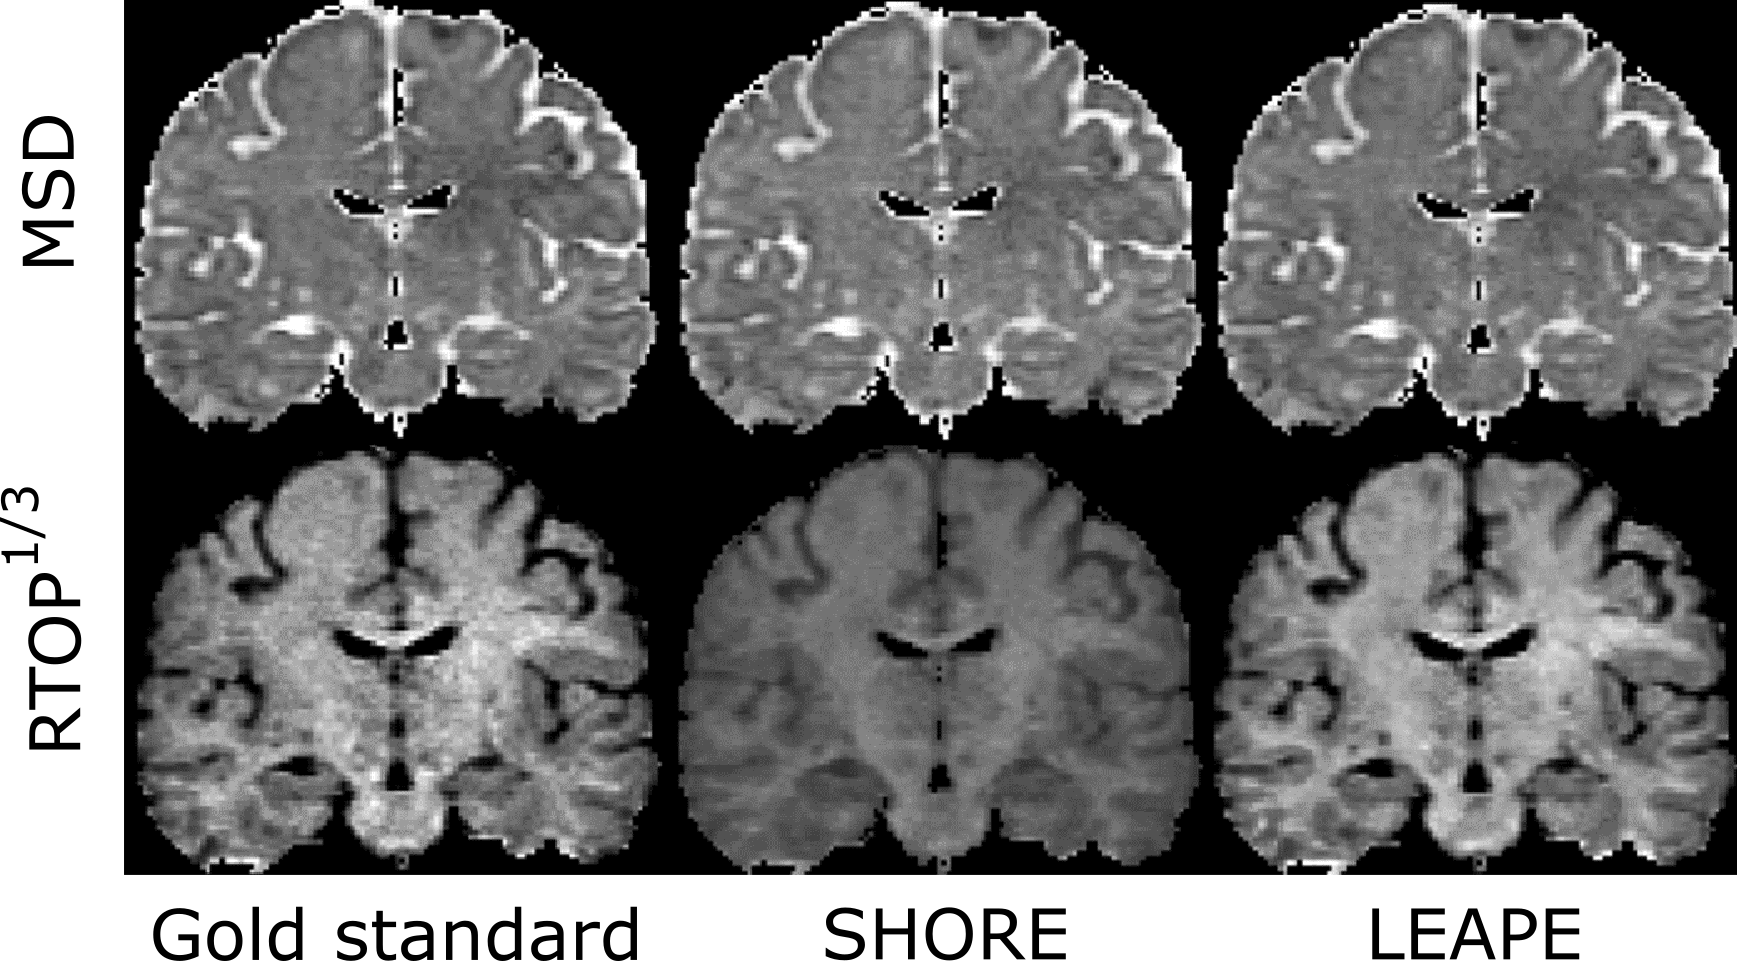

First, we evaluated the EAP estimation by examining the scalar features: MSD and RTOP. The LEAPE results on a representative subject are shown and compared with the gold standard and the results obtained by the conventional SHORE method [8] in a coronal slice in Fig. 3. Note that here for each MSD or RTOP1/3superscriptRTOP13\mathrm{RTOP}^{1/3} map, the color map is the same for the three columns. The LEAPE results resemble the gold standard. The RTOP result of SHORE is remarkably biased with the smaller set 𝒢𝒢\mathcal{G} of diffusion gradients. Then, we computed the average disagreement in the brain between the estimates and gold standard for the ten subjects, which is shown in the boxplots in Fig. 4. For both MSD and RTOP1/3superscriptRTOP13\mathrm{RTOP}^{1/3}, the LEAPE errors are smaller than those of SHORE, and the differences are highly significant (p<0.001𝑝0.001p<0.001) using a paired Student’s t𝑡t-test.

Refer to caption

Figure 3: Qualitative evaluation of MSD and RTOP in a representative coronal slice.